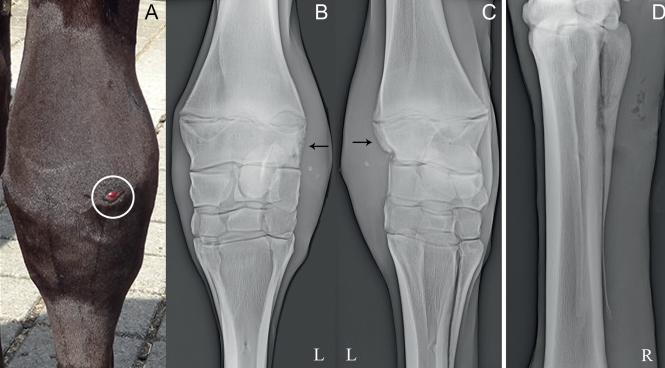

仪器检查后发现,白细胞总数增加,脓液培养可见腐生葡萄球菌生长。X光片发现其小腿部的骨组织呈现虫蚀样,通过扩创术深入了解后,确诊为骨髓炎,程度为急性状态。

实验室检查中,超声波可以提供更清晰的骨骼图像,骨骼中的脓液积聚。让兽医确定炎症的程度和需要治疗的部位。X光线可显示软组织肿胀,骨头周围纤维鞘的变化。